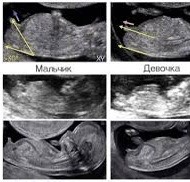

Как думаете, мальчик или девочка? Голентовский говорит девочка, но я слышала он может ошибиться)

На мальчика похож. У сына пис@ такая была. Снизу не смотрели?

@framedmi, снизу прям хорошо видно между ног